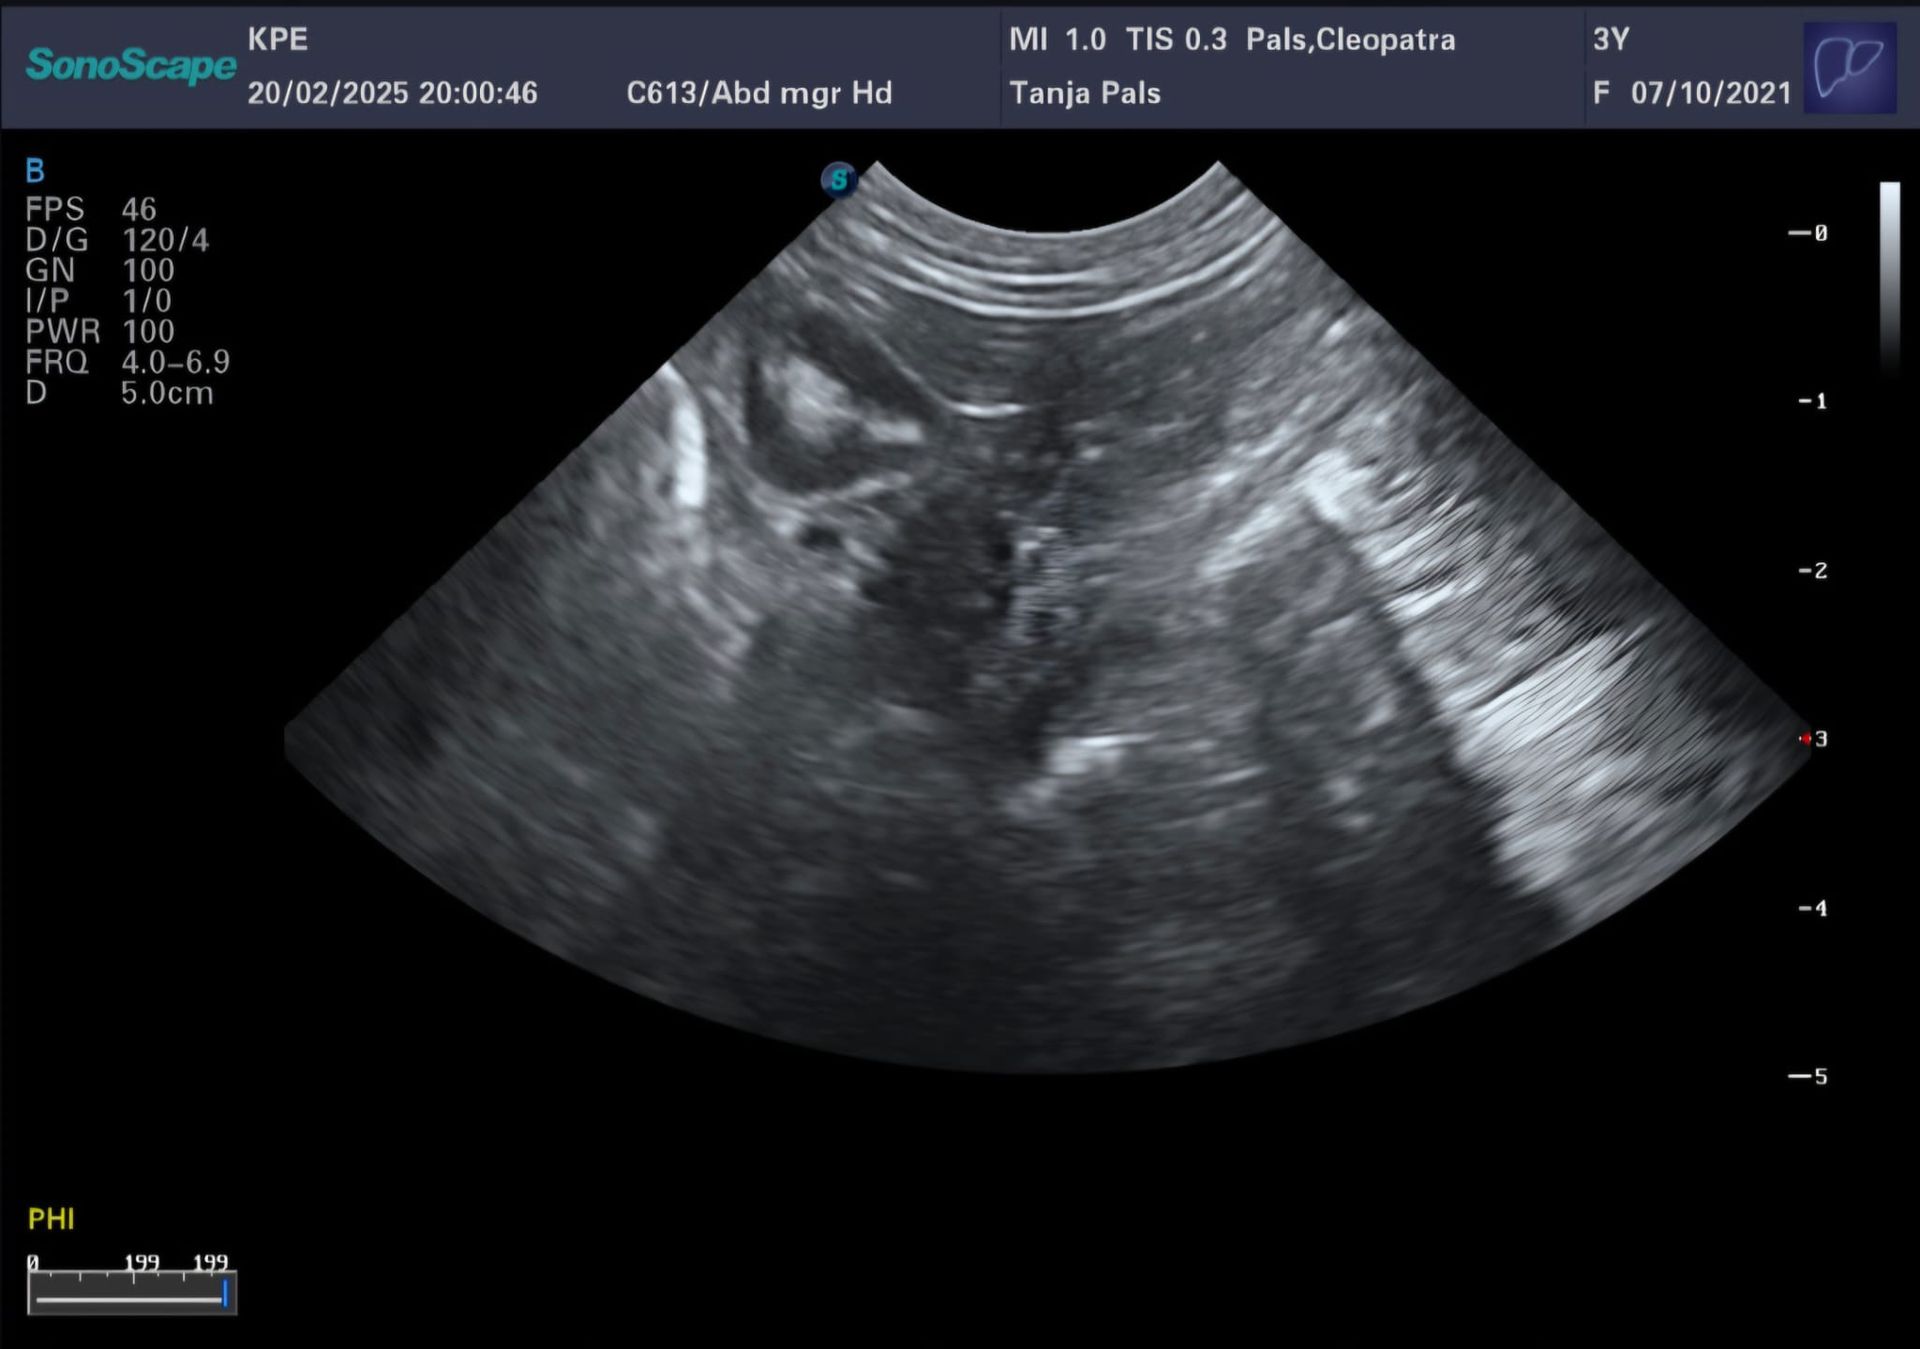

20.02.2025 schon der 24.Tag von etwa 63. Die Ultraschalluntersuchung zeigt es gibt gut erkennbare Fruchthüllen. Cleopatras Herz schlägt kräftig. Der Puls ist super. Cleopatra zeigt eine erhöhte Durchblutung. Super Voraussetzung um die Embryos fest in der Gebärmutter aufzunehmen. Wir sind sehr glücklich, da wir jetzt wirklich trächtig sind.